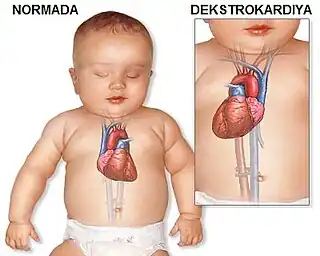

Dextrocardia (from Latin dextro, meaning "right hand side," and Greek kardia, meaning "heart") is a rare congenital condition in which the apex of the heart is located on the right side of the body, rather than the more typical placement towards the left.[1][2]

There are two main types of dextrocardia: dextrocardia of embryonic arrest (also known as isolated dextrocardia) and dextrocardia situs inversus. Dextrocardia situs inversus is further divided.

Dextrocardia situs inversus refers to the heart being a mirror image situated on the right side. For all visceral organs to be mirrored, the correct term is dextrocardia situs inversus totalis.[5][6]